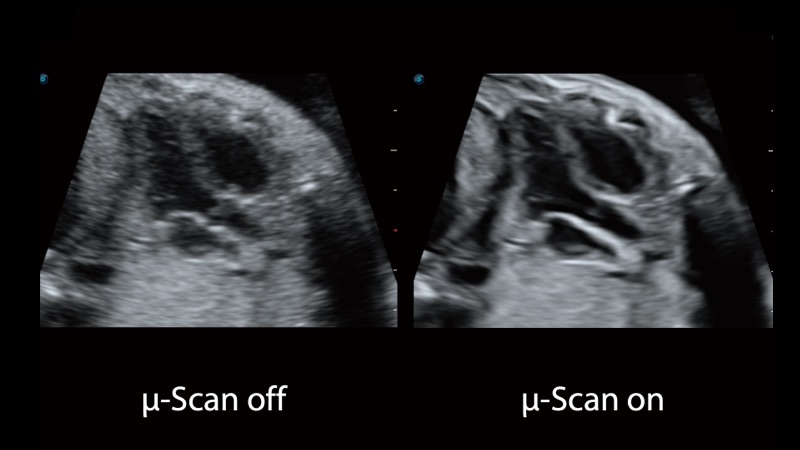

開立醫(yī)療通過不斷的技術(shù)創(chuàng)新,為大眾的生命健康提供持續(xù)關(guān)愛。P12 Plus采用全新一代超聲成像平臺,新平臺旨在將真實(shí)還原組織解剖結(jié)構(gòu)作為首要目標(biāo)。平臺采用全新集成化硬件模塊,搭載新一代芯片,系統(tǒng)性能得到大幅提升,為您的診斷提供了豐富的臨床信息。優(yōu)異的圖像表現(xiàn),豐富的探頭配置,全面的應(yīng)用功能,為您日常診斷提供了可靠的助手。